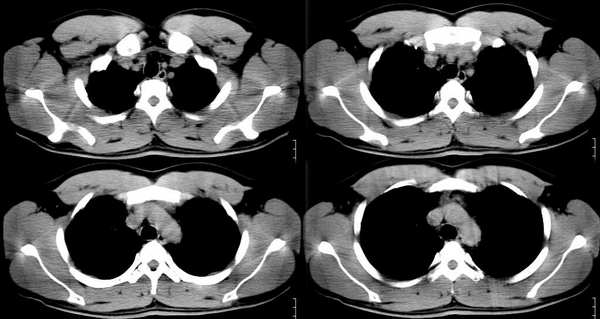

以下是引用ssl1_1在2006-3-2 22:37:00的发言:[br]肺泡蛋白沉积症(外围型)

以下是引用huangaiying1在2006-3-3 16:03:00的发言:[br]双肺弥漫分布的磨玻璃影及小结节影,以双上肺为著,纵隔内未见明显增大的淋巴结影,结合病史,考虑过敏性肺炎

以下是引用guandong在2006-3-4 20:57:00的发言:[br]两肺弥漫分布磨玻璃影,以中外带为主,可见于过敏性肺炎、肺泡蛋白沉着症、农民肺等,但不支持结核。